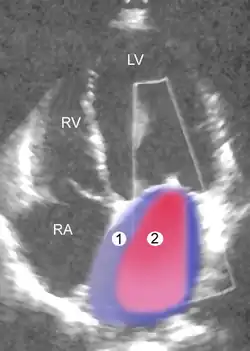

![]() |

Severe MR | Legend |

1 Left atrium (LA) – 2 MR Jet, LV Left ventricle – RV Right ventricle – RA Right atrium |

An echocardiogram is commonly used to confirm the diagnosis of MR.[16] Color doppler flow on the transthoracic echocardiogram (TTE) will reveal a jet of blood flowing from the left ventricle into the left atrium during ventricular systole. Also, it may detect a dilated left atrium and ventricle and decreased left ventricular function.[6] A transesophageal echocardiogram can give clearer images if needed as the back of the heart can also be viewed.[17]